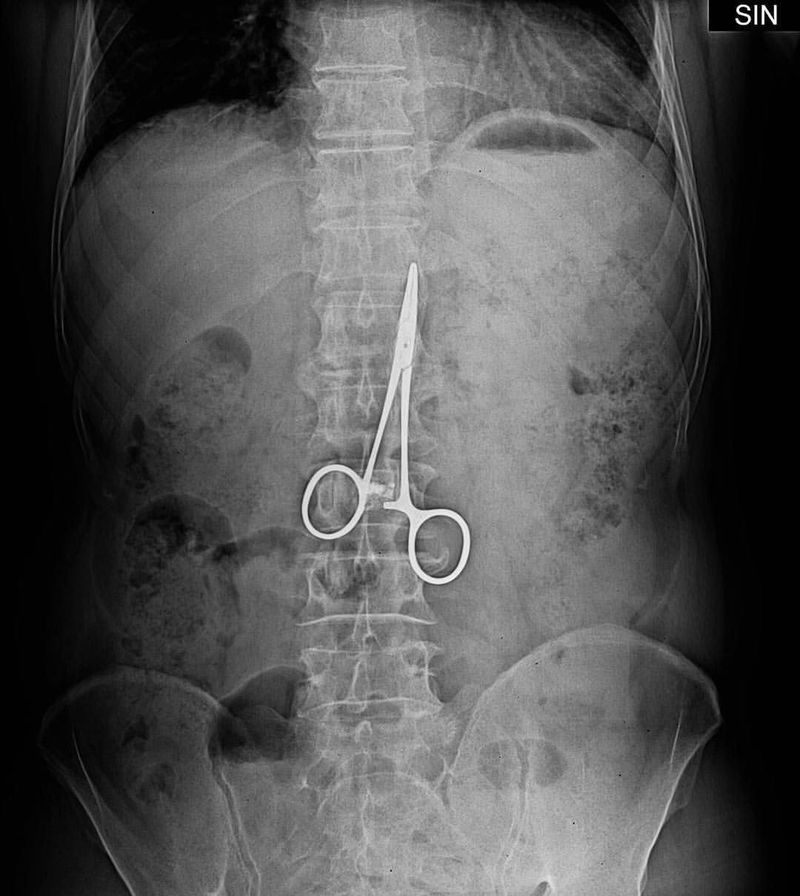

A man who went to hospital with stomach pains was found to have a surgical clamp inside his belly - from an operation 37 years before. The Chinese man had gastric ulcer surgery in 1974 and had frequently suffered stomach pains in subsequent years. He comments: "I thought it was my old stomach problems and each time I took stomach medication or anti-inflammation pills to relieve the pain." With the pains getting worse he went back to hospital - and doctors discovered the 10cm long instrument before removing it in a two hour operation. According to doctors he was lucky because part of the abdominal wall had wrapped around the clamp from development of post-surgical adhesions, preventing it from moving and potentially causing serious internal injuries.